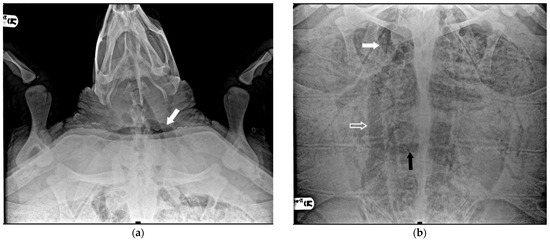

Specifically, eight animals were classified as negative (27.6%): they exhibited no radiographic signs of gas presence in any of the considered districts. In the case of 11 turtles, gas was observed in only a few anatomical areas, primarily in the marginal-costal vessels and/or renal vessels, leading to their classification as mild cases (37.9%) (Figure 1).

Figure 1.

R-ray examination in DV projection of a loggerhead turtle affected by mild GE. It is possible to detect a small amount of gas within the renal vessels (indicated by white arrows).

Four subjects were classified as having moderate severity of GE (13.8%): in addition to the renal and marginal-costal vessels, a notable distribution of gas was identified in several other vascular districts, including hepatic vessels, inferior mesenteric artery, gastric artery, abdominal transverse vein, iliac arteries, and veins (Figure 2).

Figure 2.

X-ray examination in DV projection of a subject diagnosed with moderate severity GE reveals the presence of gas in various vessels, including the gastric vessels (white arrow), inferior mesenteric artery (white empty arrow), iliac vessels (black arrow), and duodenal vein (black empty arrow). The present gas overlaps the lungs’ cranial area, reducing the visualization of lung volume.

Six turtles were categorized as severe (20.7%) because, apart from all the more peripheral districts, a significant presence of gas was observed in central vascular districts such as the precava vein, postcava vein, venous sinus, left atrium, pulmonary artery and vein, pulmonary trunk, aorta, and brachiocephalic trunk (Figure 3).

Figure 3.

X-ray examination in DV projection of a subject diagnosed with severe GE. An evident massive presence of gas in the majority of vessels: (a) the white arrow shows the subclavian artery; (b) the white arrow shows the massive presence in the precaval vein, the white empty arrow the postcava vein, the black arrow the transverse vein, obscuring a full view of the lung areas.